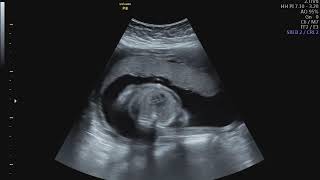

Ecografia 22 semanas varon. A carinha do seu bebé já está formada mas ainda não tem pestanas nem sobrancelhas visto que de momento tem apenas uns pelinhos brancos. Durante a semana 22 de gravidez o seu bebé mede cerca de 25 centímetros e pesa cerca de 400 gramas. No te preocupes si no tienes la oportunidad de realizarte la ecografía en ésta semana puedes hasta en la semana 22.

Llega uno de los momentos más esperados de tu embarazo. Durante la semana 22 de embarazo descubrirás muchos de sus movimientos favoritos tu bebé mide unos 25 centímetros y pesa alrededor de 400 gramos. Ecografia 20 Semanas Varon Imagui.

La ecografía que se realiza entre las 18 y las 22 semanas de embarazo sirve para comprobar no sólo el sexo del bebé sino también el bienestar general del feto.

La ecografía que se realiza entre las 18 y las 22 semanas de embarazo sirve para comprobar no sólo el sexo del bebé sino también el bienestar general del feto. Ecografia 22 semanas. Explora los videos más recientes de los siguientes hashtags. Imágenes y vídeo semana 22. La también conocida como ecografía de las 12 semanas sirve para confirmar el embarazo. Ecografía de 22 semanas. Les muestro la eco de mi bebé de 222 donde al parecer es un varón. Semana 15 De Embarazo Nino O Nina. Eco de un bebe varon.